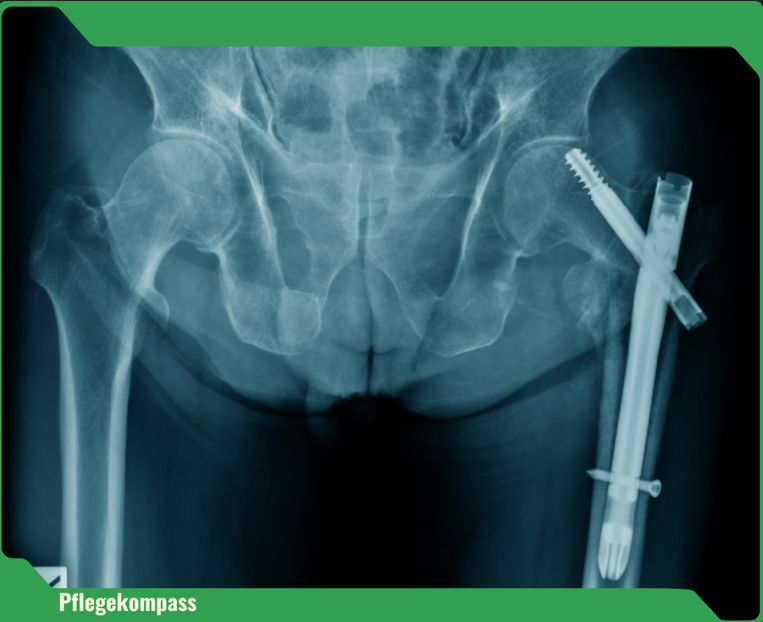

Ein Sturz bedeutet weit mehr als nur ein Ausrutschen – die Folgen reichen von Knochenbrüchen bis zum Verlust der Selbstständigkeit. Besonders häufig betroffen: der Oberschenkelhalsbruch. Über 90 % dieser Brüche entstehen durch Stürze.

Nur 40–60 % der Betroffenen mit Hüftfraktur erreichen ihre vorherige Mobilität wieder.

Menschen mit Pflegebedarf haben ein zehnfach höheres Risiko für Hüftfrakturen als Gleichaltrige ohne Pflegebedarf.